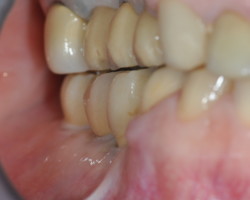

Avant-Après :